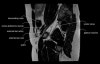

엉덩이 관절(고관절)의 MRI 단면 영상

- Coronal section

T1 Allows for evaluation of both hips simultaneously even though the patient may be symptomatic in only one hip.

T2 allows for detection of abnormal fluid in both hips which may be seen in avascular necrosis, stress fractures, muscle tears or perilabral cysts.